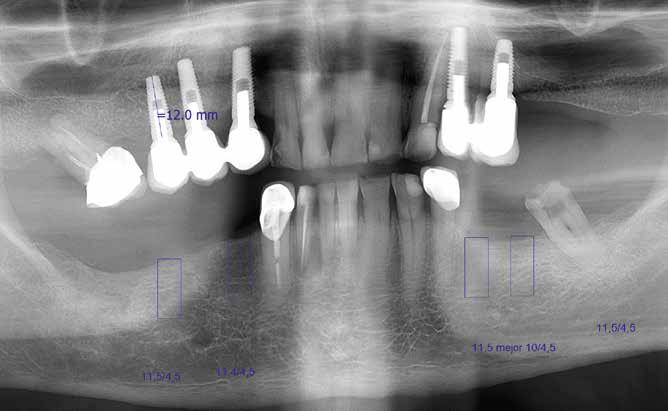

José Luis 78 éves páciensnek szüksége volt a negyedik kvadránsban hiányzó fogai pótlására. Az okklúzió kritikusnak volt ítélhető a hiányzó szemfogvezetés és a front élharapás következtében. Az antagonistán elhelyezett fémkerámia koronák növelték a túlterhelés veszélyét. A realitás azt mutatja, idősebb pácienseknél

3. ábra: Az Astra implantátumok klinikai szituációja lenyomatvételkor a 4. kvadránsban. 4. ábra: Kompozitleplezésű PEEK híd a beépített implantátumkapcsolattal.

5. ábra: Az implantátumokra okkluzális csavarrögzítéssel elhelyezett híd in situ. 6. ábra: 16 hónappal a behelyezés után ellenőrző röntgenkép.

nem lehet mindig teljes rehabilitációt végezni. Nem az esztétika, hanem a rágófunkció visszanyerése áll első helyen. Biztos választás ilyen esetben a direkt csavarrögzítéses implantátum elhorgonyzású híd, anatomikus PEEK vázzal, kompozitleplezéssel. A csonthoz hasonló rugalmassági együttható, a magas törési szilárdság és a jó biokompatibilitás a klinikai siker alapjai (4–5. ábrák). A 16 hónap elteltével elvégzett első klinikai ellenőrzés (6–7. ábrák) során a páciens kifejezte elégedettségét, a harmadik kvadránsban mutatkozó hiány zárása nem volt szükséges, a rágófunkció helyreállt. A 42-es fog gyökérkezelése sikeres volt, meggyógyult a periapikális gyulladás (8. ábra).